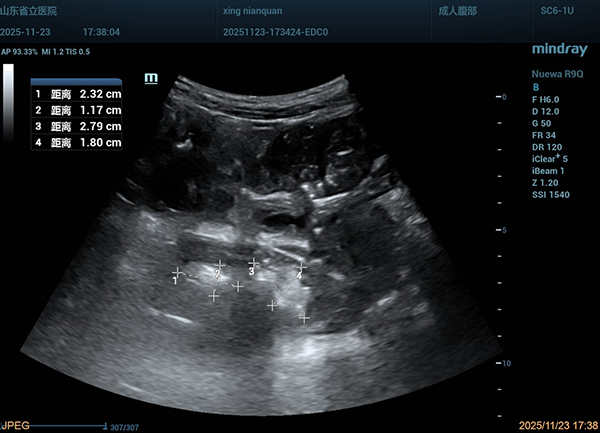

超声诊疗科主任医师刘翠红带领进修医师张修丽、相林以及规培医师、研究生等,通过胃肠超声实时动态监测,实时观察结石位置、形态变化及肠壁状况,协同调整导管位置,评估治疗效果,为治疗提供了精准的影像学依据。

治疗期间,患者对碳酸氢钠注射液反应极为敏感,出现剧烈腹痛,医疗团队应用无糖可乐以辅助溶石。由于结石松解后堵塞导管头,导致导管引流不畅,李宾主任医师多次在胃镜引导下对导管位置进行调整,保障治疗通畅。治疗第6天,患者的腹痛明显减轻。团队为患者注入香油以促进结石排出。最终,胃肠超声显示小肠结石质地变软,硬度降低,碎成三小块后经直肠顺利排出体外。当看到结石成功排出时,患者激动得热泪盈眶,说道:“谢谢你们,我终于不用开刀了,能好好吃饭、好好睡觉了!”